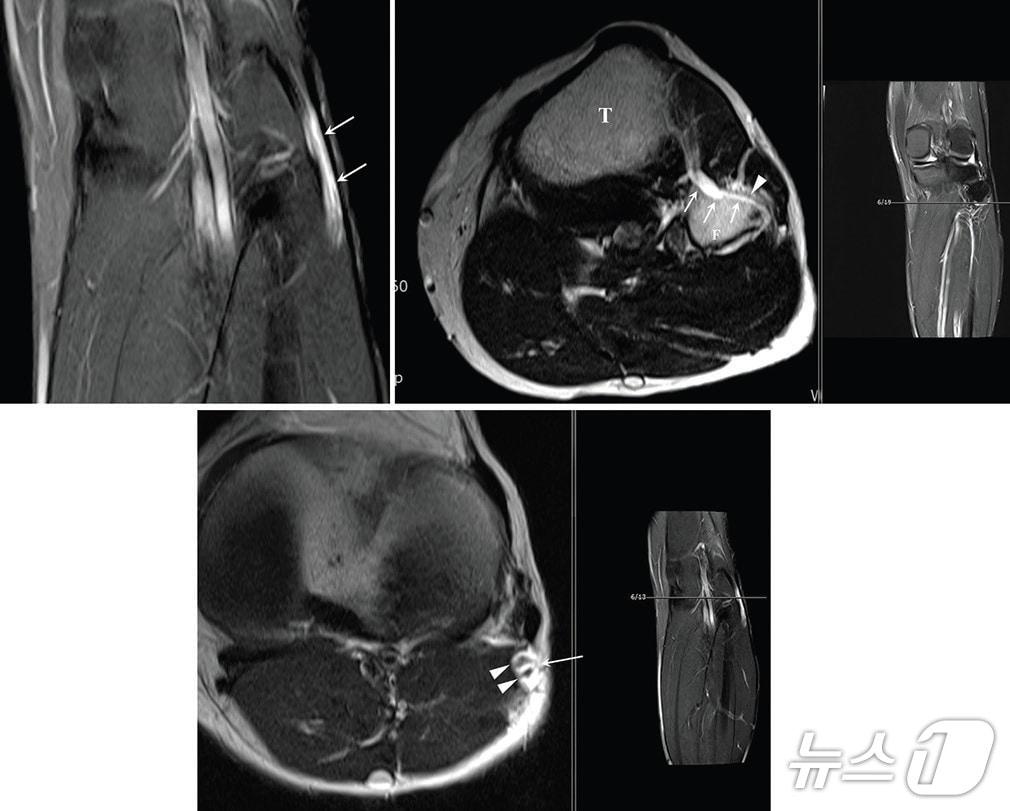

본문 이미지 - 가톨릭대학교 서울성모병원은 손병철 신경외과 교수가 최근 미국 메이요 클리닉(Mayo Clinic) 신경외과의 로버트 스피너(Robert J. Spinner) 교수팀과 공동 연구를 통해 말초신경 마비를 유발하는 신경내 결절종(intraneural ganglion cyst)의 복잡한 발생 기전을 규명했다고 13일 밝혔다.사진은 신경내 결절종의 MRI(자기공명영상) 장치 검사사진.(가톨릭대학교 서울성모병원 제공)

가톨릭대학교 서울성모병원은 손병철 신경외과 교수가 최근 미국 메이요 클리닉(Mayo Clinic) 신경외과의 로버트 스피너(Robert J. Spinner) 교수팀과 공동 연구를 통해 말초신경 마비를 유발하는 신경내 결절종(intraneural ganglion cyst)의 복잡한 발생 기전을 규명했다고 13일 밝혔다.사진은 신경내 결절종의 MRI(자기공명영상) 장치 검사사진.(가톨릭대학교 서울성모병원 제공)